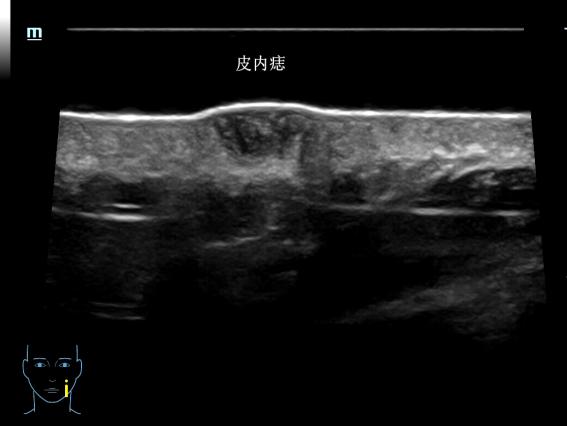

传统皮肤科诊断主要靠眼睛观察、手触摸,或取一点皮肤组织做病理检查,很难直接看到深层的情况。超高频超声(通常指频率在20MHz以上的超声),提供了新的观察维度——20MHz超高频超声可分辨0.1mm的病灶,70MHz超声高频超声可以分辨0.03mm病灶。

通过分析病灶的形态、边界特征和内部血供情况,医生能够更准确地区分炎症性病变、良性增生性病变与恶性肿瘤。